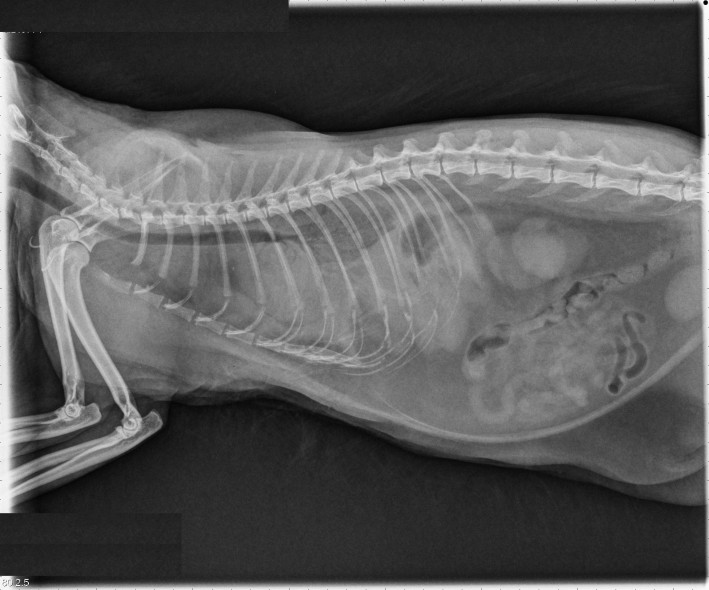

In The NewsBoundary Bay Veterinary Specialty Hospital helped out a special kitty on Sunday. Meet Gallagher, nicknamed for the area that she was found, a young female bobcat who sadly suffered a comminuted femoral fracture, leaving her unable to walk. Her injury required immediate specialized surgery if there was any hope of repairing the damage and returning […]